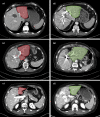

Figures